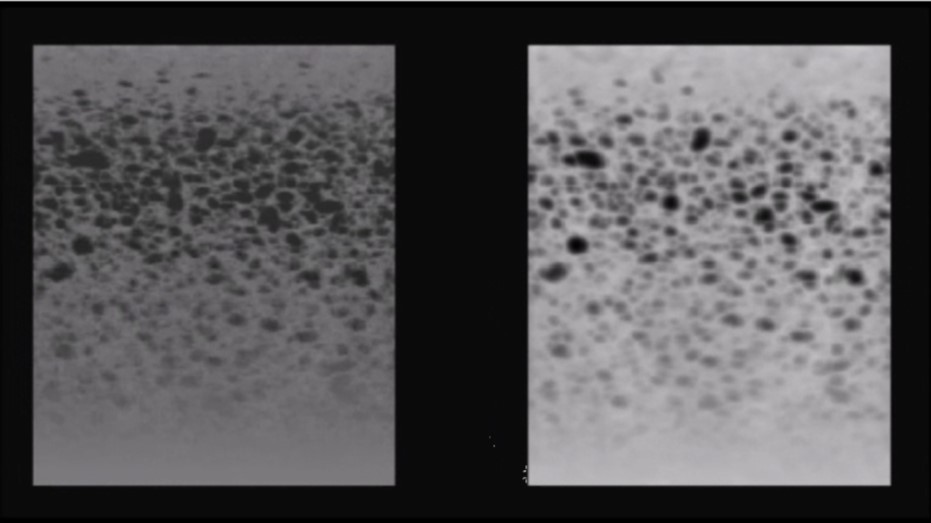

Probes with high acoustic contrast (32.63 dB to 36.66 dB) generated high quality images, Figure 3. Those with acoustic contrast values from 20 dB to 25 dB produced images of lower quality, Figure 4. A typical image produced by a damaged transducer measured as having an acoustic contrast of only 14.68 dB is shown below, Figure 5.

Figure 3.Random Void Phantom - transducer with high contrast resolution (36.66 dB, Philipps IU22.L12.5 MHz). Original 3D rendered image (left), with increased image contrast (right). Even voids within the RVP with weak contrast are discernible.

Figure 4.Random Void Phantom - medium contrast resolution (21.61 dB, Alloca SSD 5412). Original 3D rendered image (left), with increased image contrast (right).